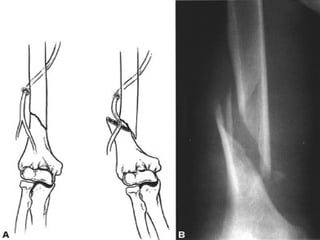

LOCALIZACION Diafisiaria Metafisiaria Epifisiaria Intraarticular Fractura-luxación

RELACION DE LOS FRAGMENTOS ENTRE SI Sin desplazamiento Con desplazamiento: lateral, angulada, rotación, diastasado, cabalgado, impactada